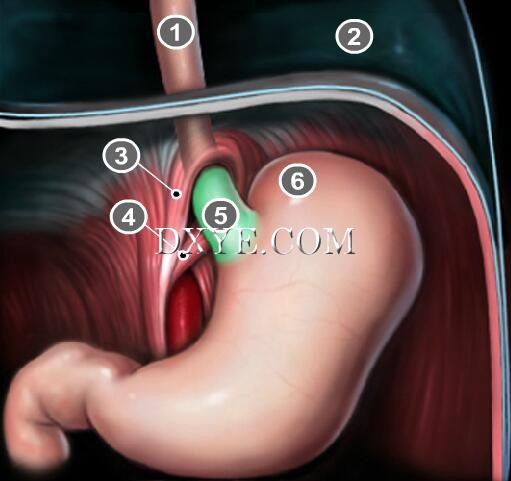

• Stage 2

Stage 2 sliding hiatal hernias occur when the gastroesophageal junction and stomach migrate above the diaphragm.

The EGV can reform above the diaphragm, preventing reflux.

This may explain reports of sliding hiatal hernias without GERD.